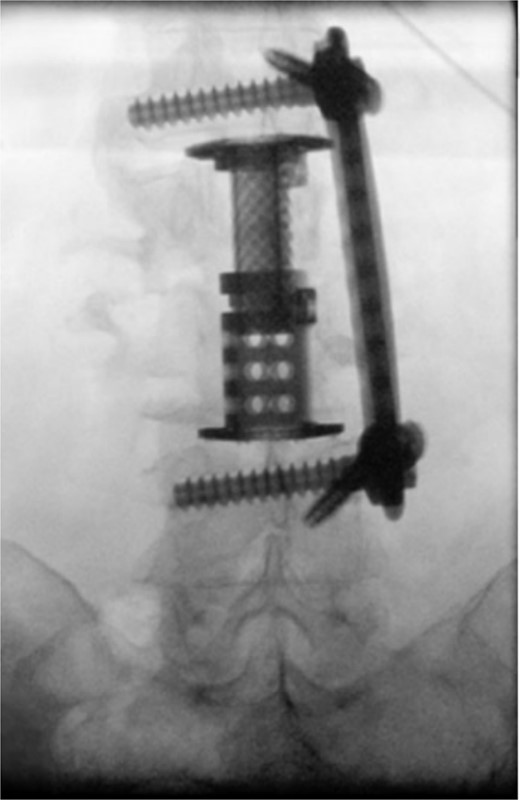

The patient was placed in the operating room for anterior lumbar interbody fusion via thoracoabdominal (TA) incision for retroperitoneal exposure. The patient was placed in the right-lateral decubitus position. The 10th rib interspace was identified, and a curvilinear incision was made from the midaxillary line and extended anteriorly and inferiorly toward the umbilicus. The retroperitoneal plane was entered, and the 11th rib was cut and morcellated for lumbar cage placement. The diaphragm was divided radially with electrocautery to further expose the abdominal cavity and retroperitoneal space. The lateral border of the psoas muscle was exposed and dissected into the anterior vertebrae L1–L4. The aorta and abdominal viscera were retracted toward the patient’s right side using an Omni retractor. Copious necrotic tissue and caseating granulomas were removed. The L2–L3 vertebrae were exposed, corpectomy was performed, and a titanium cage was placed with a plate spanning from L1 to L4 (Fig. 2A and B). To achieve added stability, a second surgery for posterior percutaneous screw placement without lumbar fusion was performed (Fig. 3). The patient recovered without complications and was subsequently discharged to a skilled nursing facility, and ultimately home. At the 1-month follow-up visit, the patient’s TA incision had completely healed, and there was no evidence of recurrent infection.

(A) Anterior intraoperative fluoroscopy demonstrating final titanium cage placement spanning from L1 to L4. (B) Lateral intraoperative fluoroscopy demonstrating final titanium cage placement spanning from L1 to L4.